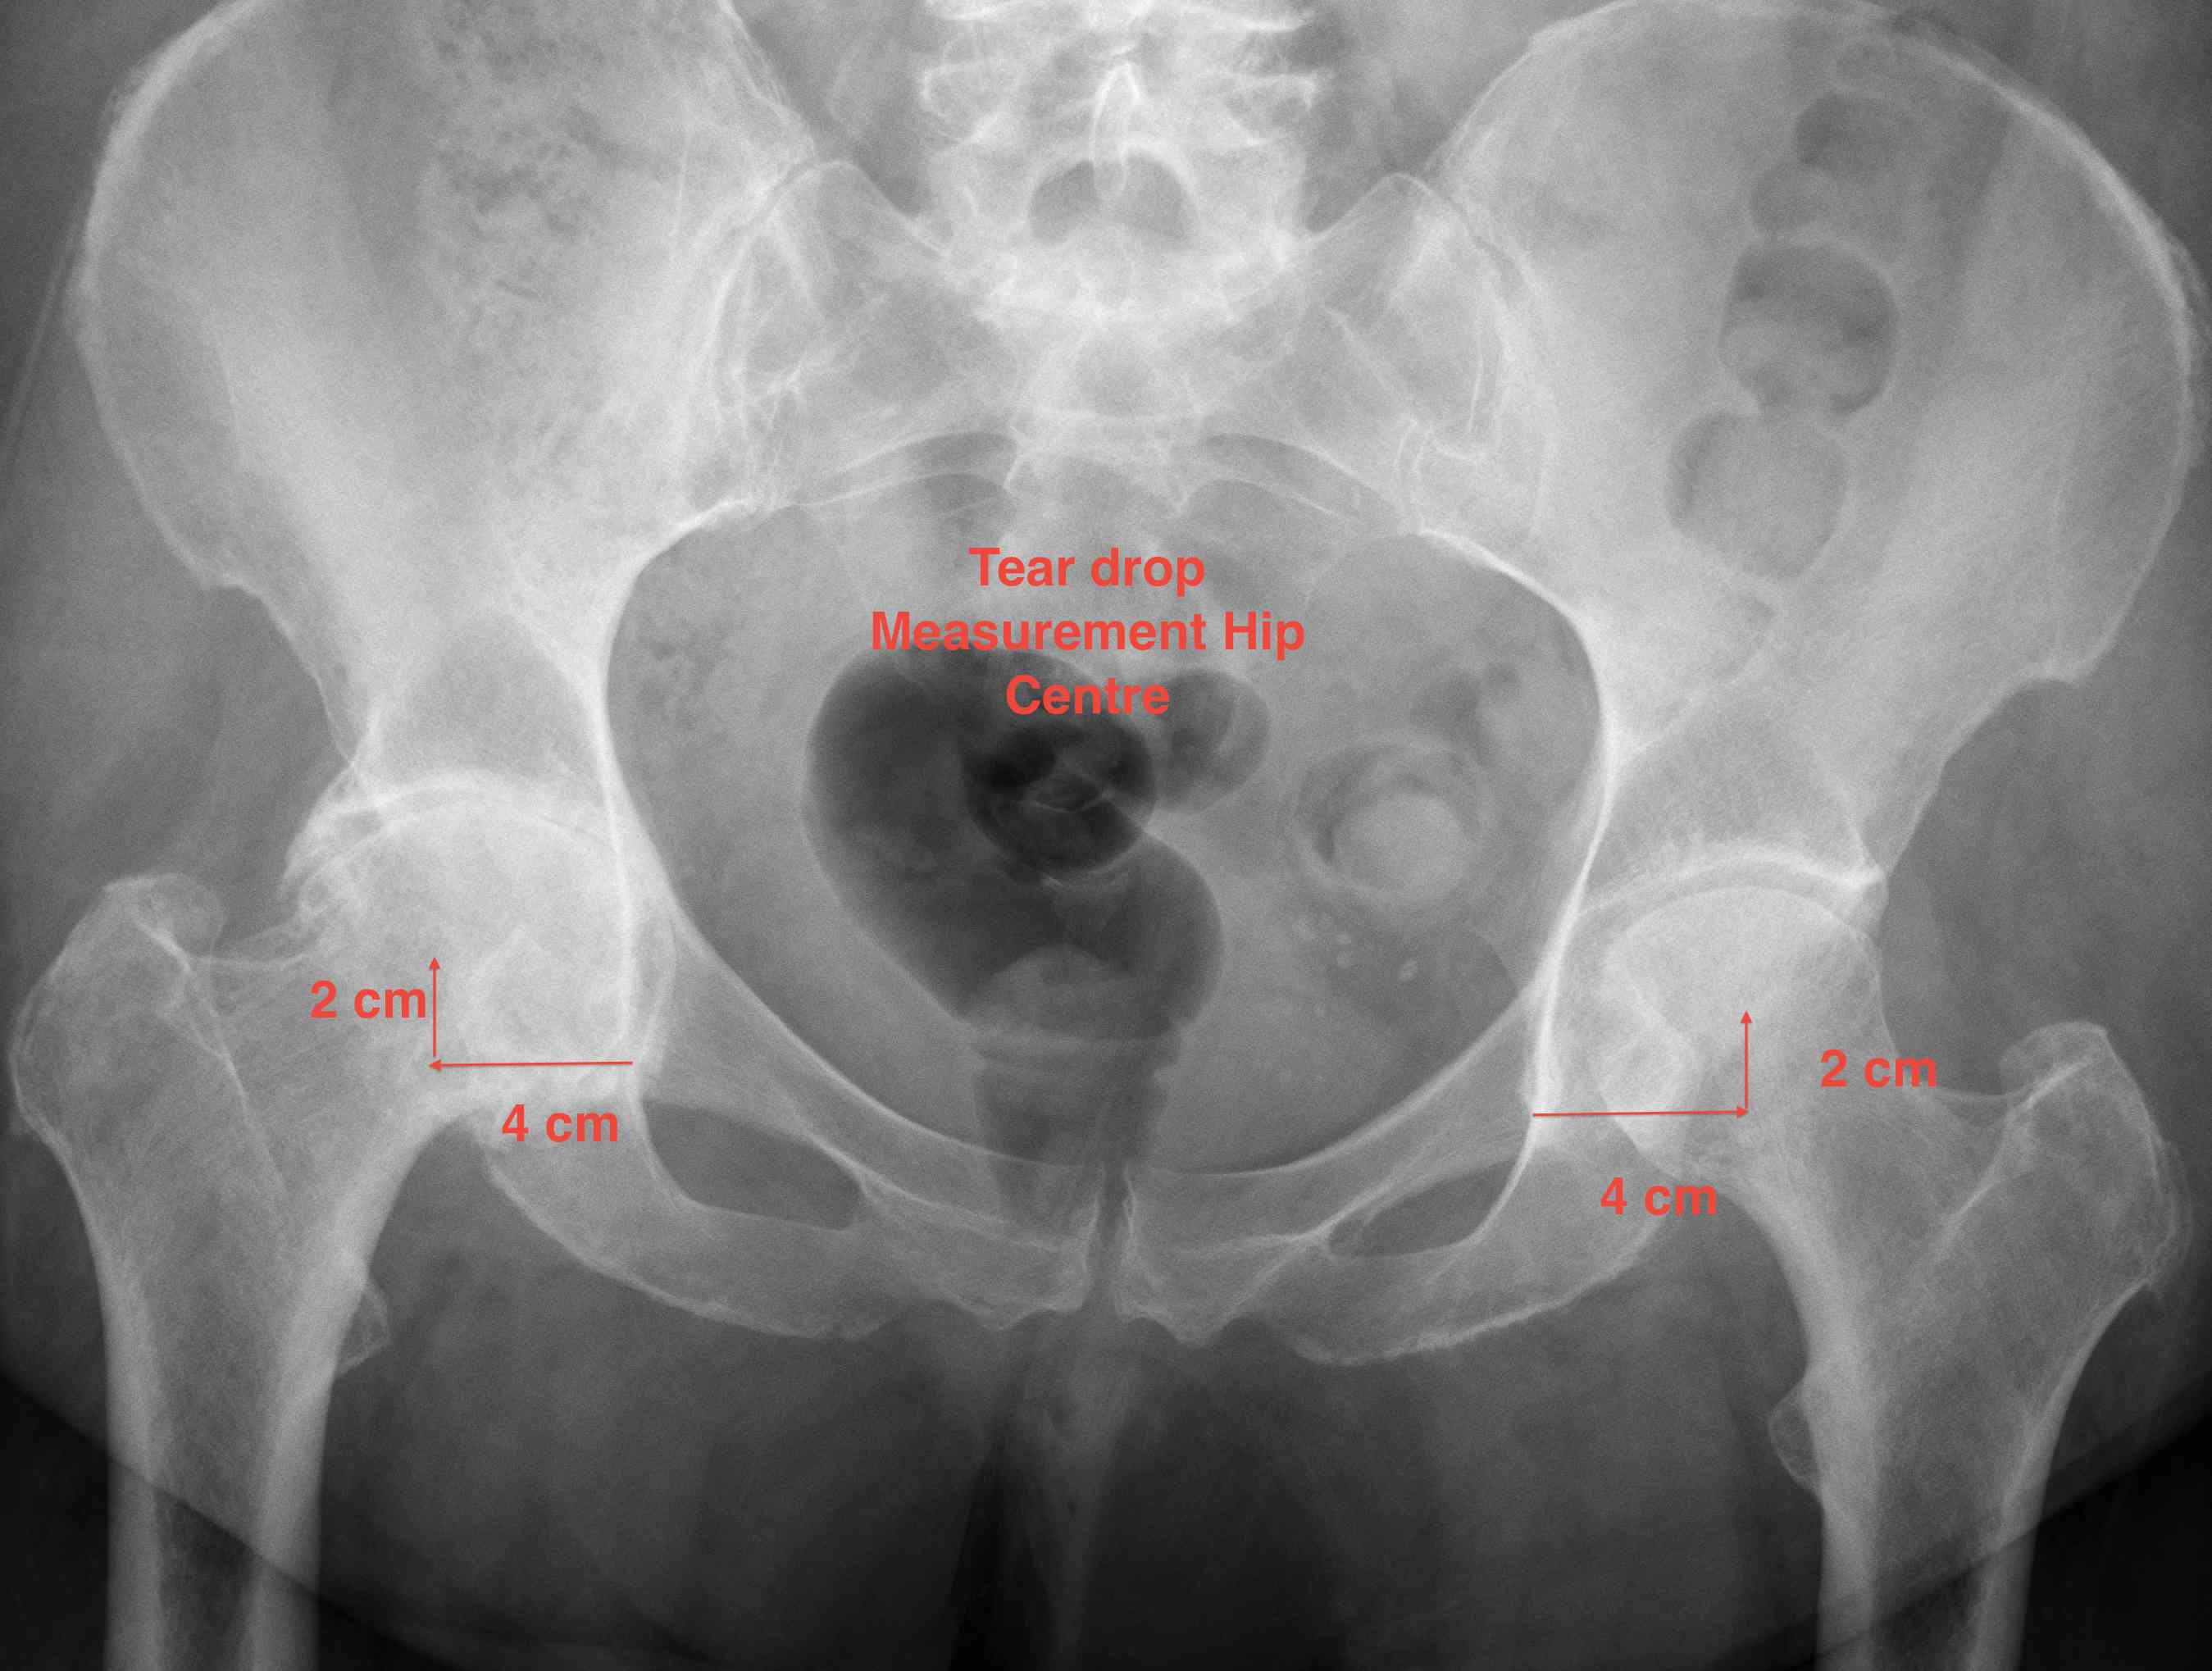

Determine Hip Centre

1. Teardrop

- average 2 cm vertical & 4 cm horizontal from teardrop